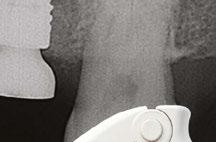

Figure 3: Preoperative panographic view of the maxillary and mandibular arches from the CBCT scan demonstrating anatomy that will impact implant placement Figure 4: Extraoral scan of the full maxillary and man dibular dentures that patient presented with, which she was unable to wear due to a significant gag reflex Figures 5A and 5B: Virtual planning of implant placement in the maxillary arch Figures 6A and 6B: Virtual planning of implant placement in the mandibular arch

A CBCT scan was taken and panoramic views of the maxilla and mandible evaluated (Figure 3). Bilateral pneumatization of the maxillary sinus was noted, but adequate bone height was present between the premolars for implant placement to support an All-on-X hybrid prosthesis. In the mandibular arch, sufficient height was available between the mental foramen bilaterally and over the inferior alveolar nerve for implant placement to also sup port an All-on-X fixed hybrid prosthesis. A discussion was held with the patient that implants could be placed in both arches that would allow restoration with fixed prosthetics. Should sufficient insertion torque be achieved at the time of implant placement, a screw-retained hybrid provisional prosthesis would be placed and worn for several months during healing after which a final prosthesis would be fabricated. The patient would also be able to do a “trial-run” of the esthetics with the provisional prosthesis, with any requested modifications made when the final prosthesis was designed and fabricated. The treatment plan included six implants in each arch to support the planned hybrid prosthe ses. The patient was informed that reduction of the crestal bone would be required to achieve a flat ridge for adaptation of the prosthesis to the ridge as well as to provide adequate interarch space for the final prosthesis. The patient accepted the treatment plan. An intraoral scan of the arches was performed with Medit i500 (Medit Corp, Seoul, Korea) as well as the current complete arch maxillary and mandibular dentures (Figure 4). The patient was dismissed and scheduled for the surgical appointment.

The scans were imported into the planning software (Real GUIDE™, Allston, Massachusetts) and merged with the CBCT scan to allow implant planning. The maxillary arch was planned for implants at six sites, including tilted implants mesial to the maxillary sinus bilaterally to avoid the need for sinus augmen tation and allow more distal placement of the implant platform for a better anterior/posterior (A-P) spread (Figure 5A). ULT implants were planned as follows: No. 3 (3.75 x 11.5 mm), No. 6 (3.75 x 11.5 mm), No. 8 (3.75 x 11.5 mm), No. 9 (3.75

The mandibular arch was then planned for seven possi ble implants with the extra implant beyond what was initially planned should the short posterior implant on the patient’s left have less than ideal initial stability to provide better stability of the provisional prosthesis (Figure 6A). Ditron Dental ULT implants were planned as follows: No. 19 (3.75 x 11.5 mm), No. 20 (3.75 x 11.5 mm), No. 22 (3.75 x 11.5 mm), No. 24 (3.75 x 11.5 mm), No. 25 (3.75 x 11.5 mm), No. 27 (3.75 mm x 10 mm), and No. 30 (3.75 x 11.5 mm) (Figure 6B). A replica of the current dentures was fabricated to be used as a surgical guide, and the center of the replica was removed with a lab bur to create a zone for the implants to emerge to ensure they would be within the proper prosthetic zone (Figure 7).